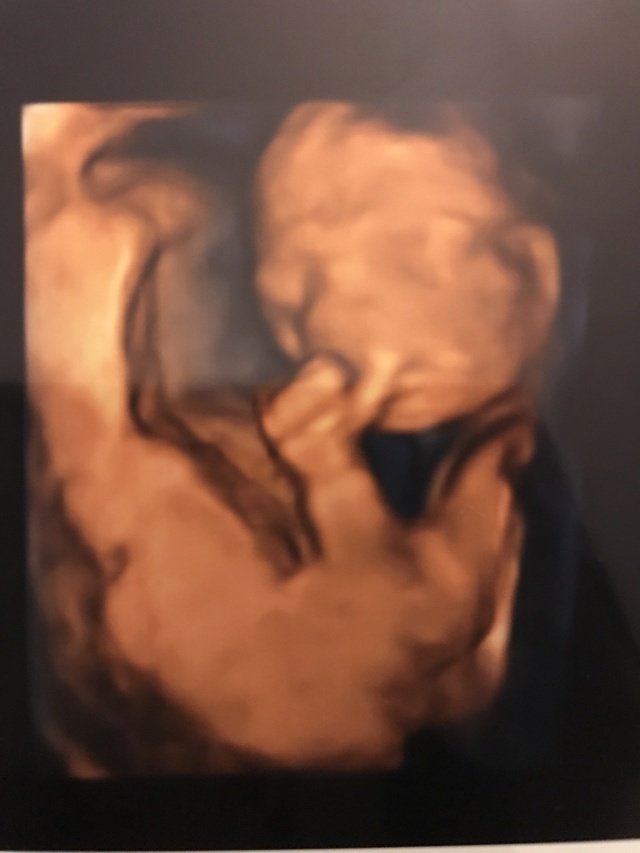

20週5日(20w5d・男の子)|たくさき3710 さん(28歳)

初めての4Dエコーでお顔を見れるのをとっても楽しみにしていました!ですが胎盤に顔を押しつけるようにしたままあまり動かず、ほぼずっと横顔しか見せてくれませんでした。

このエコーはその中でも貴重な、少しだけこっちを向いてくれた瞬間の物で、偶然左手の親指をしゃぶっていました! 次は34wで4Dエコーの予定なので、お顔をたくさん見せてくれるといいな!